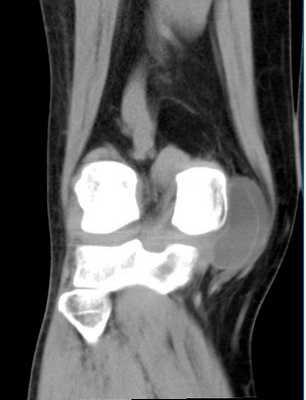

МСКТ коленного сустава (коронарная проекция)

Фото МСКТ коленного сустава в первую очередь показывают кости (бедренную, мало- и большеберцовую, надколенник). Также на снимках можно увидеть:

внутри- и внесуставные связки.